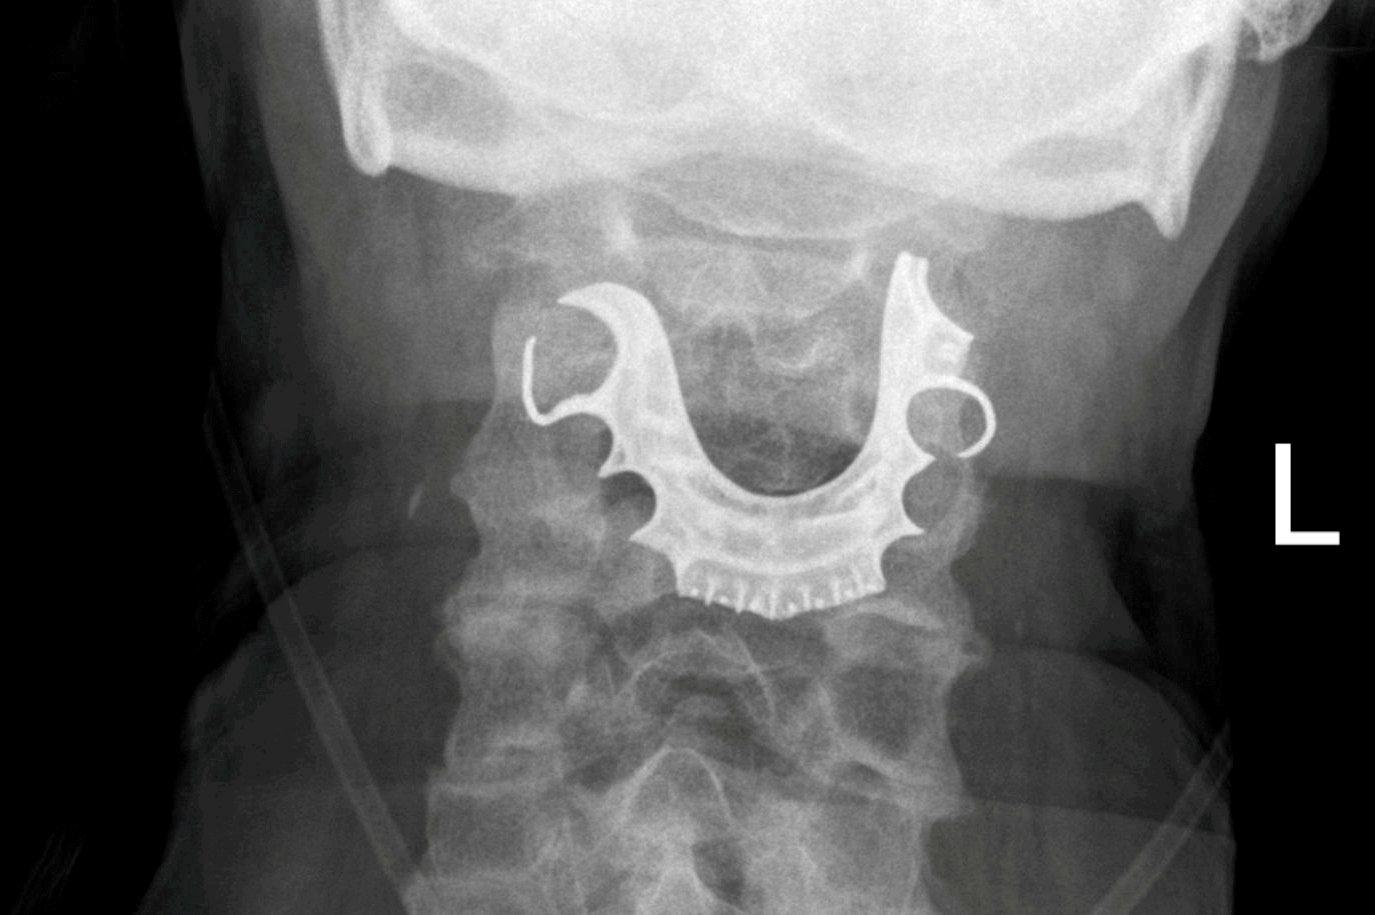

The problem, an X-ray eventually revealed, was rather more obscure: the man had breathed in his own false teeth and they were lodged in his larynx.

But when he came back several days later now unable to either swallow or breathe properly, doctors suspected he may have contracted pneumonia from inhaling something foreign. They inserted a flexible tube through the man’s nose, and – to both his and their surprise – found a metallic plate covering his vocal cords.

“On explaining this to the patient, he revealed his dentures had been lost during his general surgery admission eight days earlier and consisted of a metallic roof plate and three front teeth,” the report states.